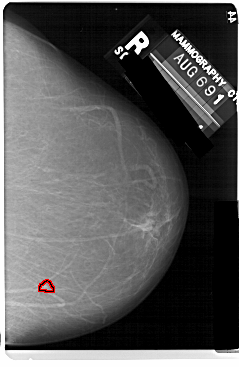

A_1111_1.RIGHT_MLO

RIGHT_MLO LINES 5491 PIXELS_PER_LINE 3721 BITS_PER_PIXEL 12 RESOLUTION 43.5 OVERLAY

FILE: A_1111_1.RIGHT_MLO.OVERLAY

TOTAL_ABNORMALITIES 1

ABNORMALITY 1

LESION_TYPE MASS SHAPE ROUND MARGINS ILL_DEFINED

ASSESSMENT 4

SUBTLETY 3

PATHOLOGY MALIGNANT

TOTAL_OUTLINES 1

BOUNDARY